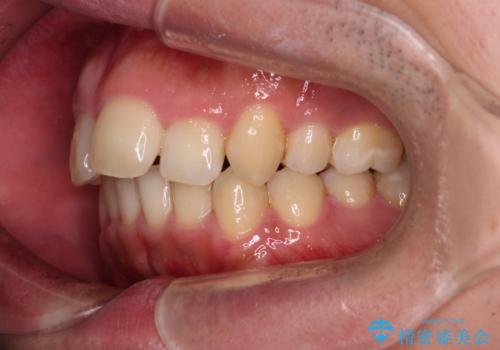

- 学生時代に抜歯矯正した歯列が後戻りしてきたとのことで来院された患者様です。

舌の突出癖が原因で上顎前歯が前方に移動したと考えられたため、舌のトレーニングを徹底して行っていただきながら、後戻りを解消していくこととしました。

マウスピース矯正でもワイヤー矯正でも対応可能でしたが、患者様の希望によりワイヤー装置による矯正治療を行うこととしました。

ワイヤー矯正ということで、上顎大臼歯を後方に移動するための補助装置を併用して、積極的に前歯を引っ込めていくこととしました。